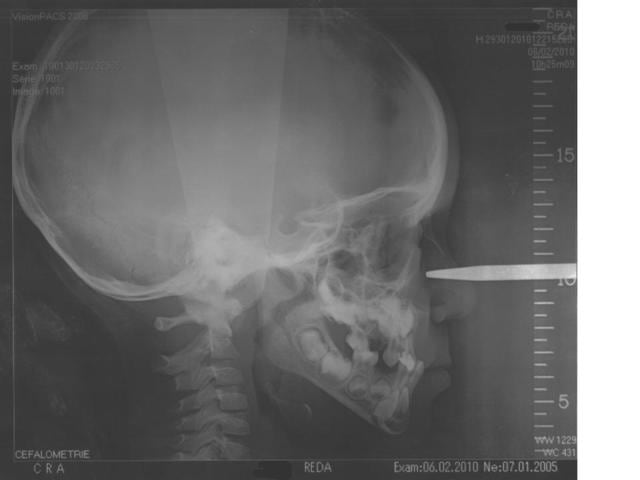

Le cas ne semble pas dramatique. classe I squelettique. Antecondylie significative qui peut laisser penser effectivement à un proglissement.

C'est un patient mésofacial et non brachy. C'est une classe III par déficience du développement du maxillaire et non pas une classe I. Concernant l'analyse de Rickets les valeurs sont données pour des patients agés de 9 ans et plus, donc je ne sais comment certains l'utilisent pour un patient de 5 ans.

Pour l'instant pas de gros décalage squelettique. classe I en rapport à f1m et f1M de l'analyse de Delaire. (pas de statistiques).

Put1 vous êtes trop forts les mecs!! 5 photos ( pas terribles ) ...une télé ( peu lisible )... et vous faites un diagnostic et un plan de traitement!